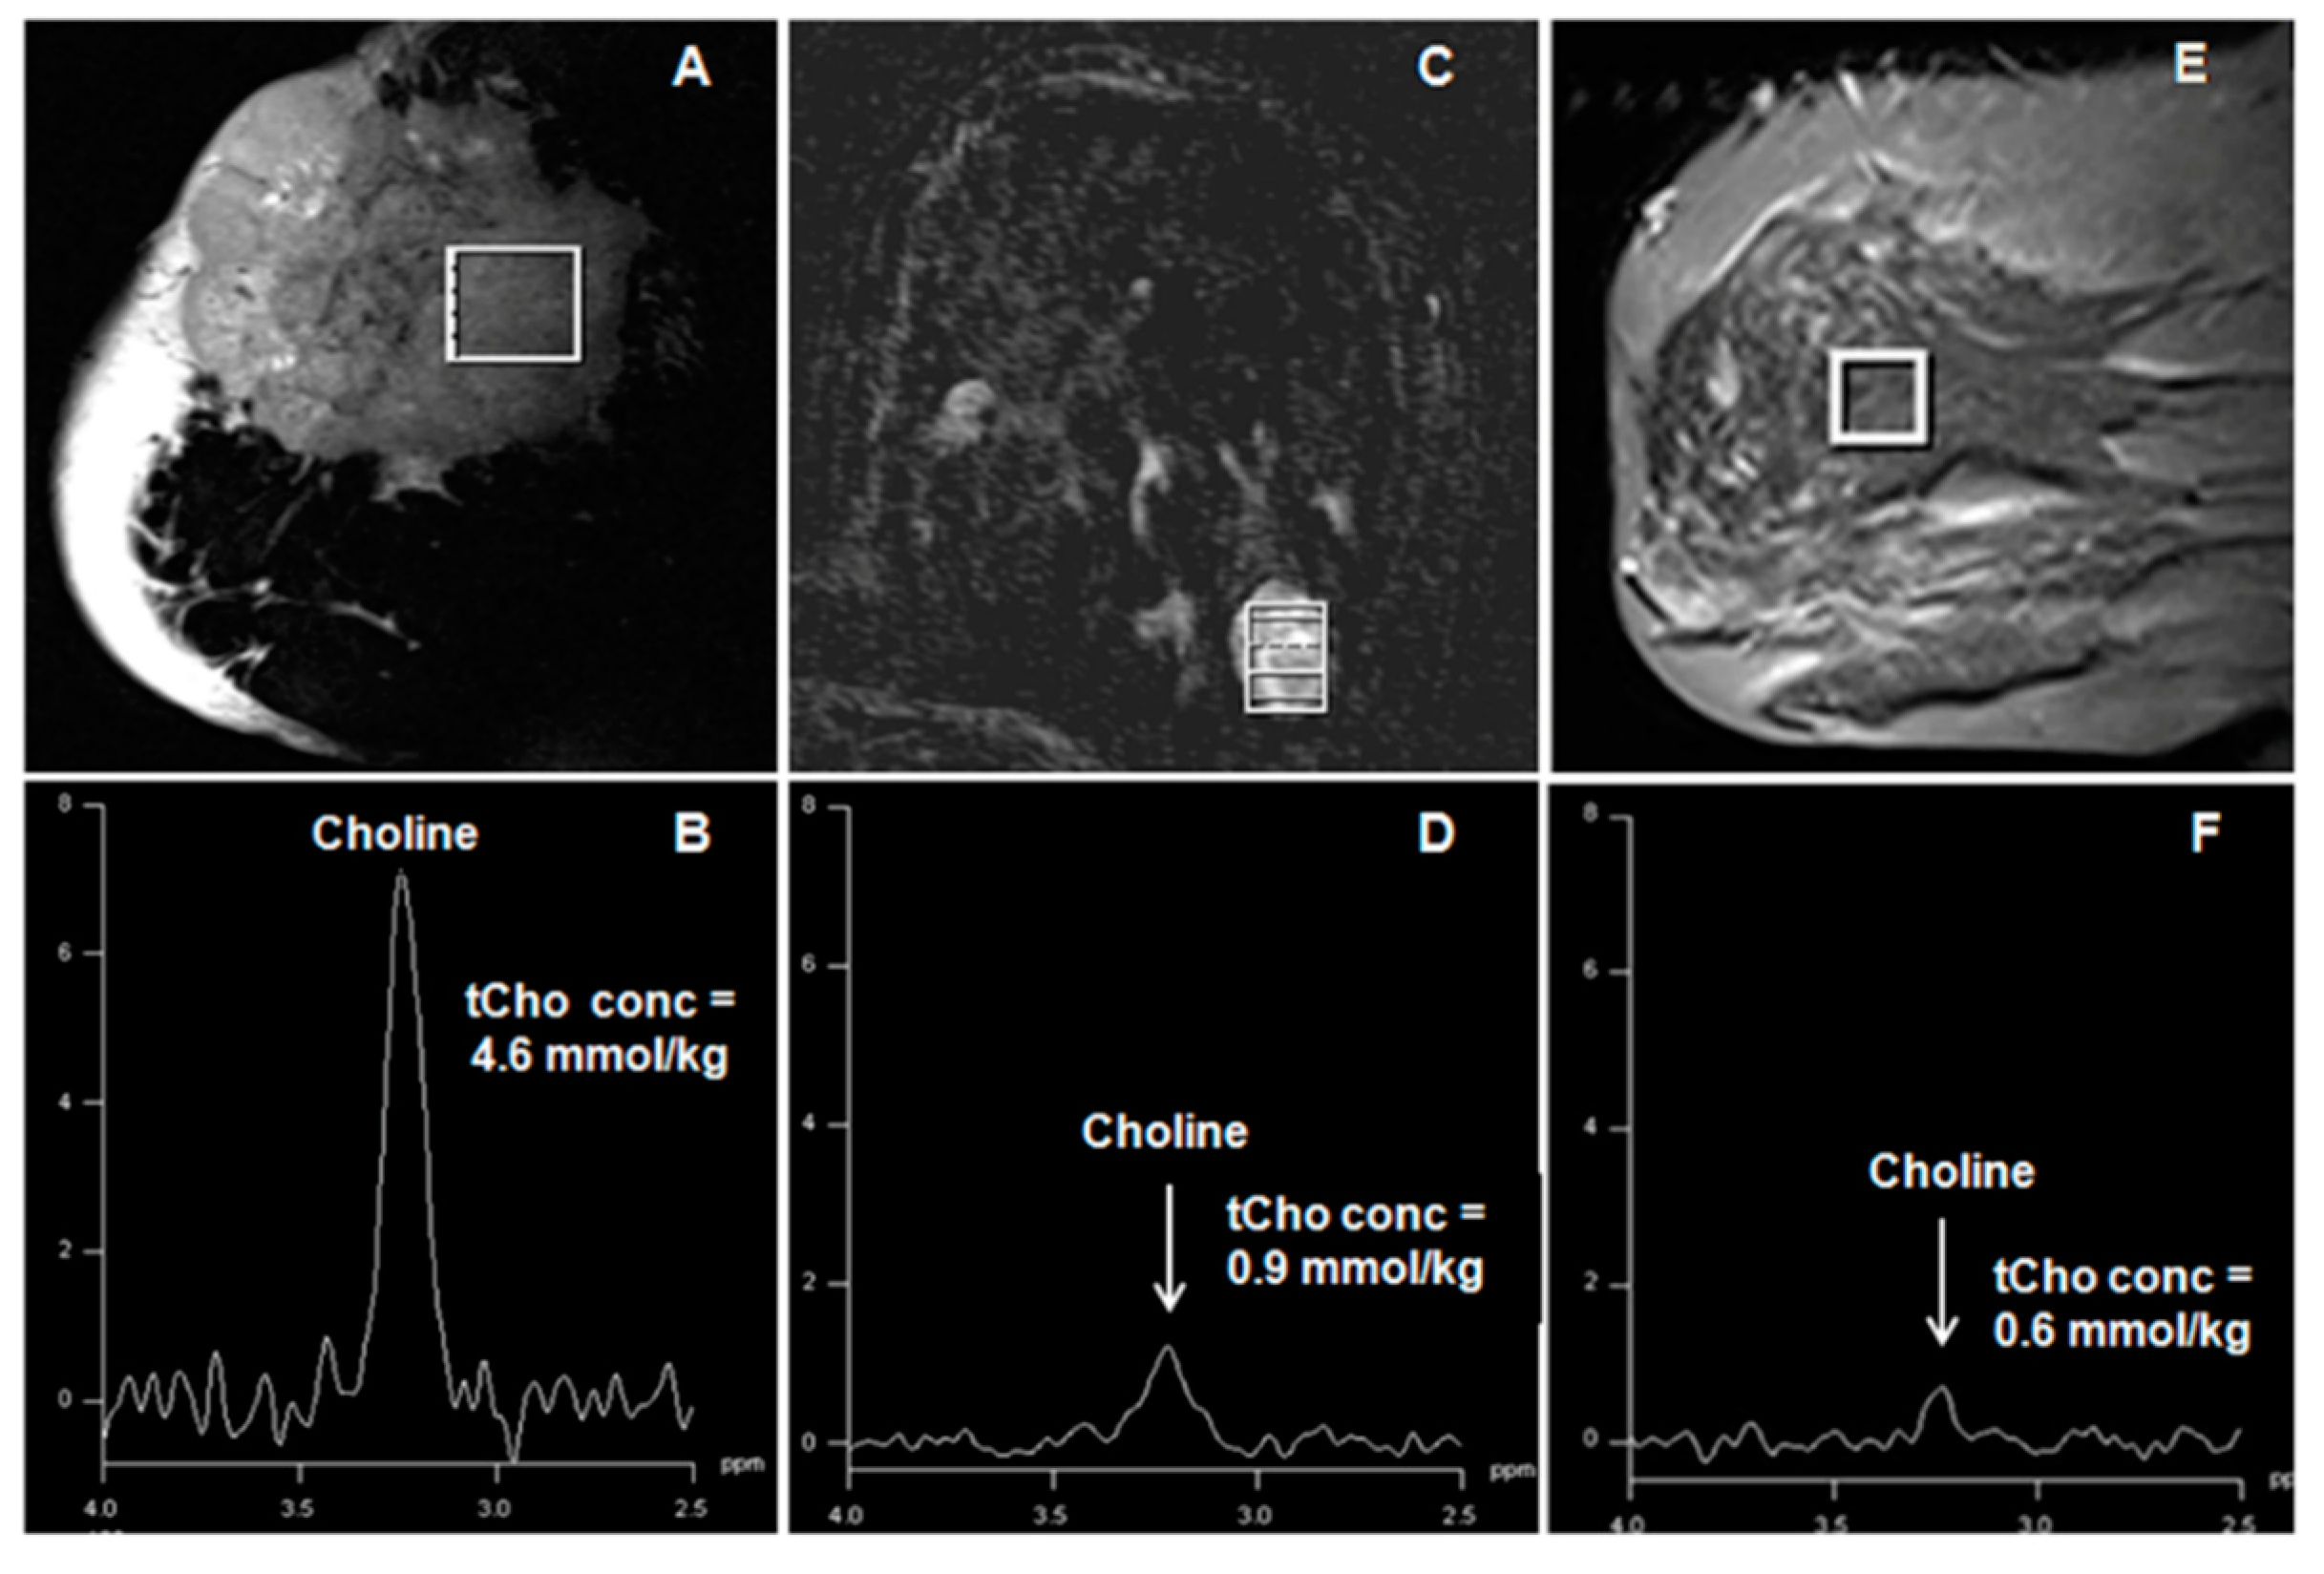

- Jagannathan, N.R.; Kumar, M.; Seenu, V.; Coshic, O.; Dwivedi, S.N.; Julka, P.K.; Srivastava, A.; Rath, G.K. Evaluation of total choline from in vivo volume localized proton MR spectroscopy and its response to neoadjuvant chemotherapy in locally advanced breast cancer. Br. J. Cancer 2001, 84, 1016–1022. [Google Scholar] [CrossRef] [Green Version]

- Sah, R.G.; Sharma, U.; Parshad, R.; Seenu, V.; Mathur, S.R.; Jagannathan, N.R. Association of estrogen receptor, progesterone receptor, and human epidermal growth factor receptor 2 status with total choline concentration and tumor volume in breast cancer patients: An MRI and in vivo proton MRS study. Magn. Reson. Med. 2012, 68, 1039–1047. [Google Scholar] [CrossRef] [PubMed]